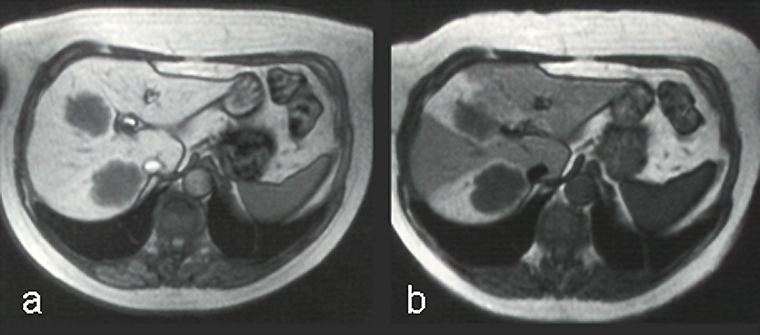

Ferumoxides, or super-paramagnetic iron oxides, are negative enhancers taken up by the normal liver, which contains reticuloendothelial cells, but not by lesions that lack reticuloendothelial cells (Figure 13-15) [⇒ Paley; cf. iron oxides].

Figura 13-15:

Example of a negative liver contrast agent (ferumoxide). This particulate agent is taken up by en­do­the­lial and Kupffer's cells. They darken the liver tissue due to their effective shortening of the T2 relaxation time.

T2-weighted GRE: (a) precontrast; (b) postcontrast. The liver metastases are well delineated on the post-contrast image; with this agent, the normal liver tissue becomes black.